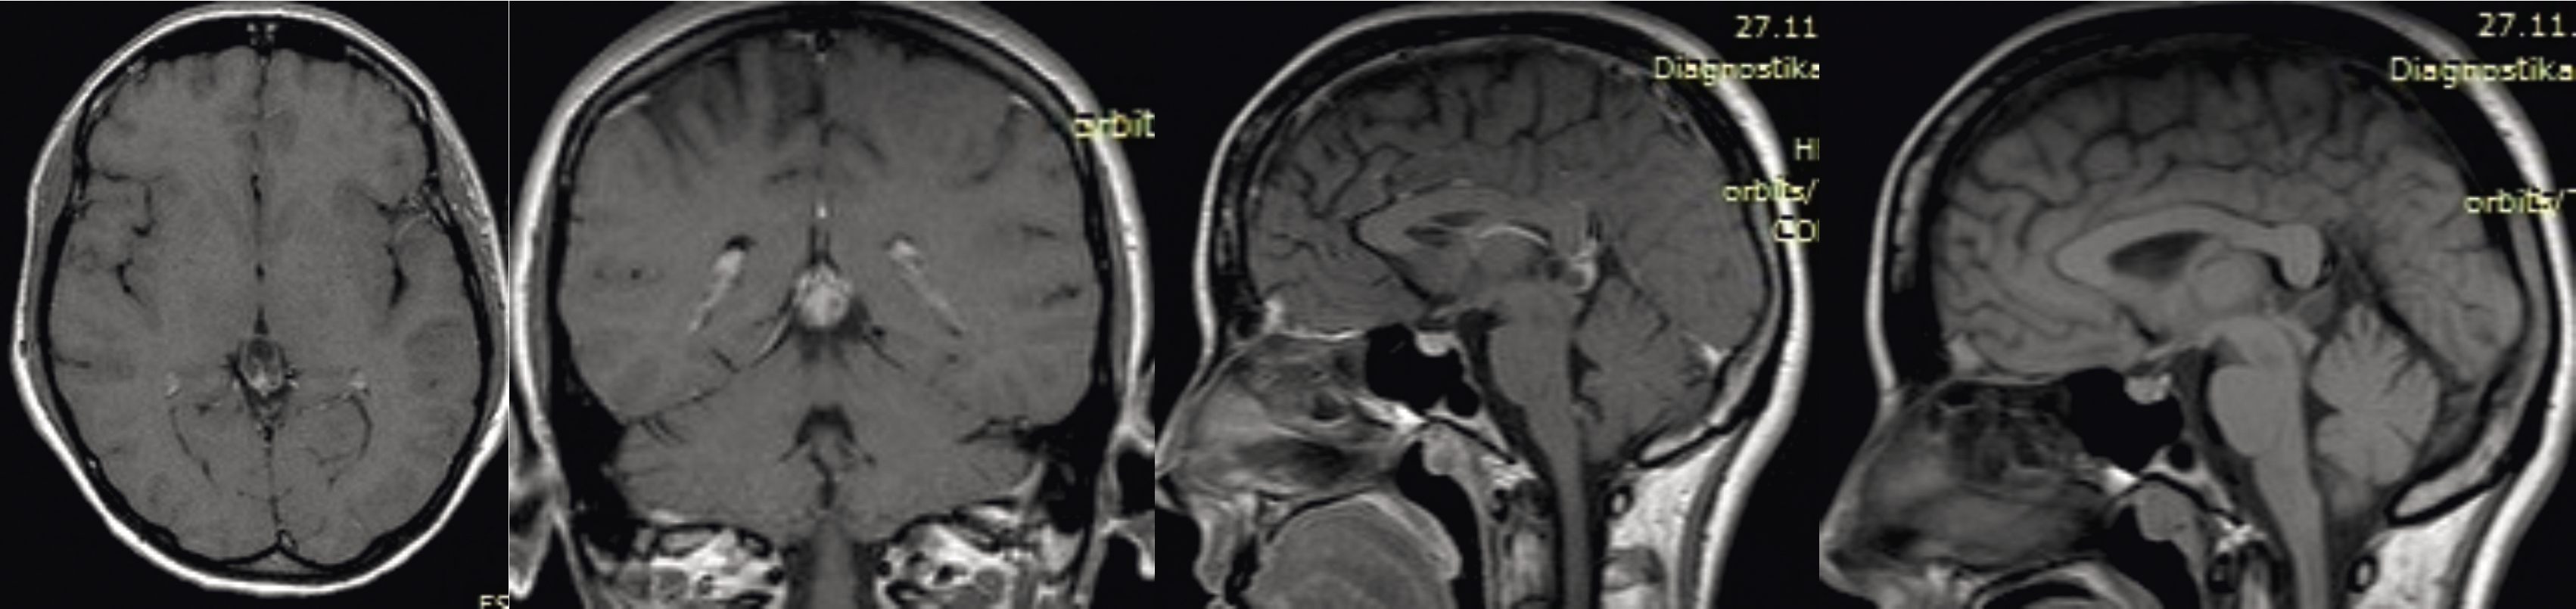

Данные МРТ-исследования больной до операции: в пинеальной области по средней линии визуализируется крупное солидно-кистозное объемное новообразование эпифиза с распространением на III желудочек с дислокацией четверохолмия с блоком ликворопроводящих путей, развитием окклюзионной тривентрикуломегалии (рис. 3).

Рис. 3. МРТ головного мозга с внутривенным контрастированием до операции удаления опухоли эпифиза